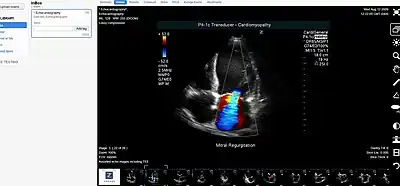

- Picture archiving and communication system (PACS) - A medical imaging technology that provides economical storage of, and convenient access to, images from multiple modalities within a facility.